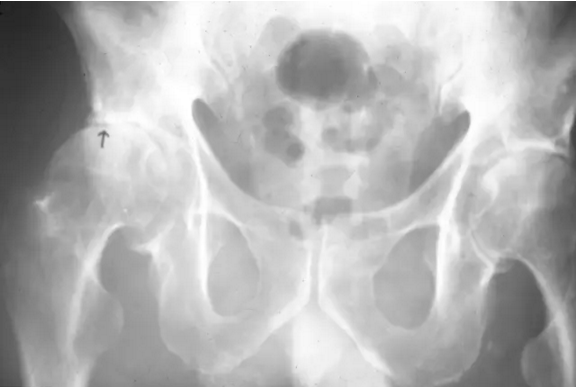

骨盆的前后视图显示右股骨头的外侧部分因缺血坏死(箭头)扁平,相邻关节空间变窄,近关节硬化和代表退行性关节疾病的骨赘。

在股骨头缺血性坏死患者的骨盆正位平片可见不对称关节间隙狭窄(箭头),近关节硬化,软骨下囊肿形成围绕右髋继发退行性骨关节病。